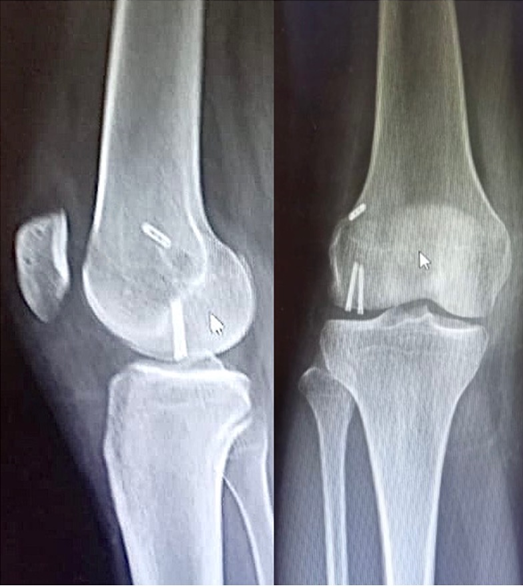

A 20-year-old male (dimensions) presented to our emergency department following a direct injury to his right knee, which occurred while playing basketball. He complained of a click in his right knee joint while playing the sport, which was associated with a suspected lateral patella dislocation that spontaneously relocated. This was associated with severe pain and swelling of the right knee joint. The patient was unable to bear weight following the injury and was brought to our emergency department immediately afterwards. On examination in the emergency department, the patellar appeared relocated, and he had some amount of lateral laxity and apprehension, but it was difficult to assess the laxity due to the swelling of the right knee joint. The patient had tenderness on the lateral aspect of the knee along with inability to move the knee through the range of motion (ROM) more than 0–40° of ROM due to pain and swelling. He was comfortable at 20° of flexion of the knee joint. The patient reported no previous episode of patella dislocation, but did report some injury to the same knee 5 years ago; but he did not have any details of the incident. On examination for generalized laxity, his Beighton Score was 6/9, which corresponds to excessively hypermobile. Fig. 1

Figure 1: Radiographs on presentation of the patient to our emergency room – right knee anteroposterior and lateral view.

The patient was administered painkillers and ice fomentation and underwent an X-ray of his knee joint. An osteochondral fragment was visible in the knee joint, but we were not able to determine where the origin of the fragment was. A computed tomography scan of the knee joint was performed, and the fragment was identified to be originating from the distal LFC and was measuring 2.5 cm × 2.5 cm. The Insall Salvati ratio was 1.36, and the Caton Deschamps Ratio was 1.6. The Tibial Tuberosity–Trocheal Groove (TT–TG) distance was 20 mm, and his knee was a Dejour type B. A standing scannogram was not possible for the patient due to pain. The decision to avoid a tuberosity osteotomy was made as the TT-TG distance was just at the borderline with a slightly high Caton–Deschamps index. The decision to perform a lateral parapatellar arthrotomy with a strong medial patellofemoral ligament (MPFL) reconstruction was deemed sufficient to maintain patella stability. The final decision would be taken intraoperatively after tightening of the MPFL graft regarding the requirement of a tuberosity osteotomy. Fig. 2, 3.

Final tightening of the MPFL graft was done by pulling the tensioning threads. A confirmatory shoot was taken through the fluoroscopy machine to confirm the fragment reduction and the position of the Herbert screws. Fig. 9.

Figure 10: Immediate post-operative radiographs of the right knee.

The patient was given a compression dressing and a long knee brace post-surgery for the post-operative period. The patient was advised to start knee range of movement exercises from the following day to allow for the lateral arthrotomy not to fibrose and cause excessive lateral tightness. He was advised 4 weeks of non-weight bearing with a walker/crutch and was advised to switch to partial weight bearing after 4 weeks post-surgery. The patient was followed up at 4 weeks to start partial weight bearing and a regular follow-up. He had achieved ROM up to 90° but had developed a 10° flexion deformity. He was advised aggressive physiotherapy, prone extensions, and quadriceps strengthening. He followed up at 6 months with full extension achieved and a range from 0°to 120°. He was still complaining of pain on and off, but had resumed all activities, including playing racquet sports regularly. There were no episodes or any feeling of patellar instability. The osteochondral fragment was holding well and had achieved radiological union. The patient was advised to follow-up at 1 year. Fig. 11.

Figure 11: 6 months follow-up X-ray of the right knee showing healing of the fragment.